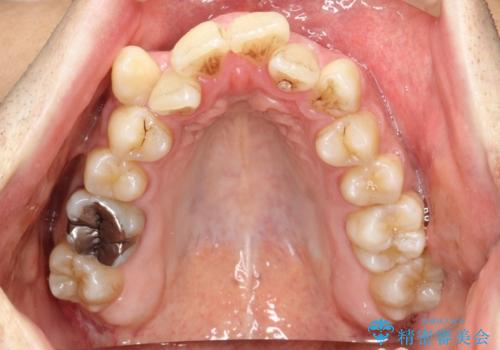

- 前歯のガタガタと八重歯を治したいということで矯正を希望された患者様です。

骨格的に上顎骨が小さいために相対的に下顎骨が前に出ていたため、歯の傾きなど理想的な仕上がりが難しく、外科矯正ではなく歯列矯正の場合はカモフラージュ矯正になること説明の上、矯正治療を進めることになりました。

上顎は左右5番抜歯、下顎は左右4番抜歯しています。

途中までは下顎は全体にワイヤーをはらずに、セクショナルワイヤーにて治療を進めています。

上顎は最初から全体にワイヤーをはっていましたが、上顎前歯部の歯肉退縮のリスクが高そうだったために、途中まで下顎と同じくセクショナルワイヤーで進めています。